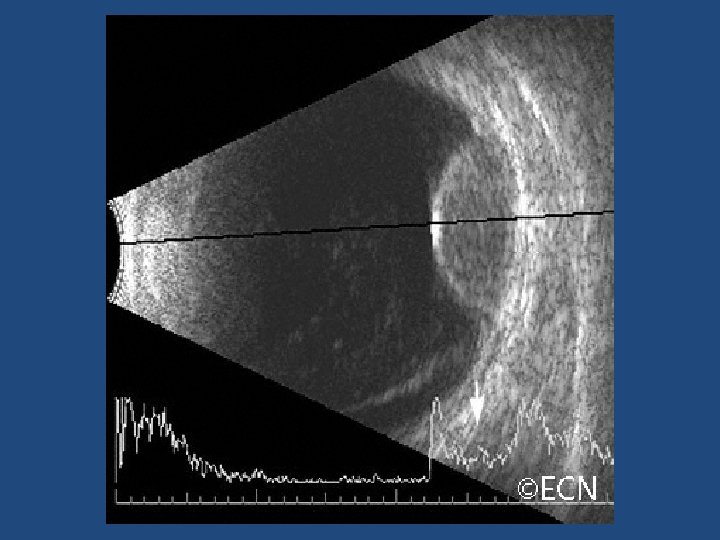

Other risk factors • Ultrasonographic hollowness • Thickness > 1. 5 mm • Suspicious OCT findings (p<0. 001)

Ultrasound vs OCT-EDI • OCT-EDI measurements are approximately 50% less thick than USB measurements (i. e. a 3 mm lesion on USB will measure 1. 5 mm on OCT-EDI) • USB cannot detect/measure lesions <0. 75 mm thick – these can be measured with OCT-EDI • OCT-EDI less helpful as tumours enlarge (>3 mm) • The lesion must be at least 1. 5 mm thick on USB measurement before meaningful comments on echogenicity can be made • USB echogenicity is determined by the density of cellularity of the tissue comprising the lesion (the denser the tissue the lesser the internal reflectivity) • OCT-EDI appearance is determined by the amount of pigment in the lesion and does not correlate to ultrasonic internal reflectivity • OCT-EDI offers a better estimate of the true dimensions of the lesion compared to USB